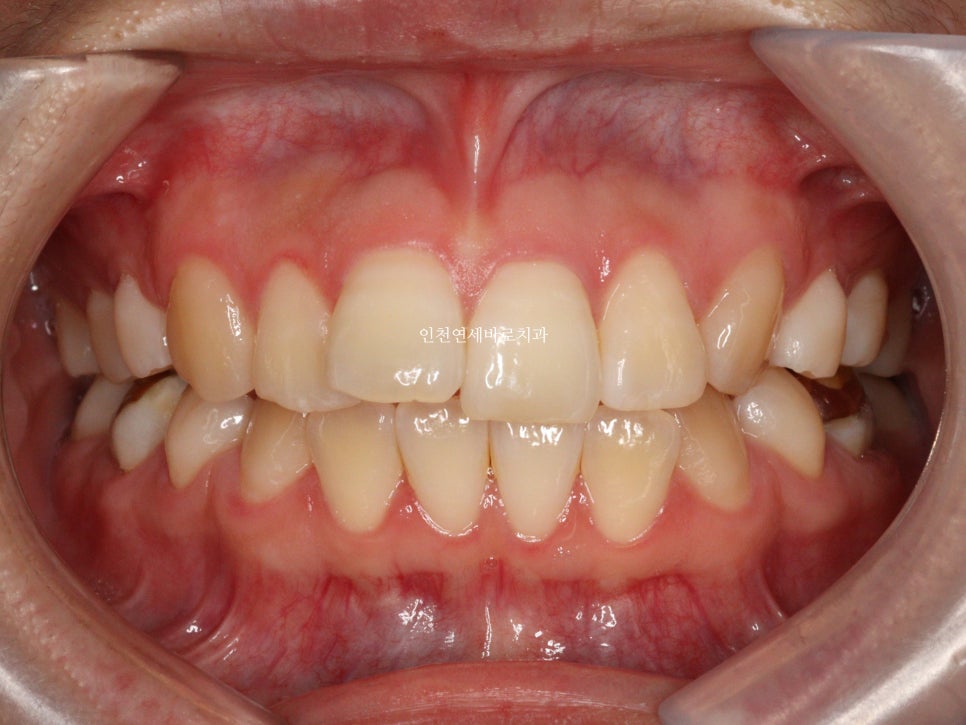

변화모습입니다.

약 3개월의 변화모습입니다.

그리고 치료가 마무리 된 후의 모습입니다.

위 환자분의 재교정 치료기간은 약 7개월입니다.

7개월동안 병원은 두번 왔구요.